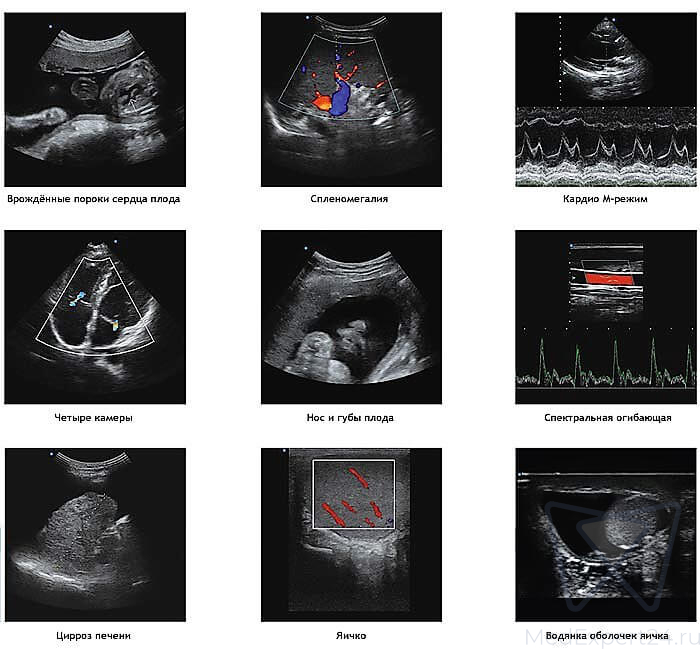

Обновленная модель ультразвукового сканера Apogee 3800 производства компании SIUI получила не только обновленный дизайн, но и новые функциональные возможности, что позволило значительно улучшить качество визуализации.

- В экспертном сканере Apogee 3800 реализованы передовые интеллектуальные решения, которые совместно с новейшими технологиями визуализации откроют перед Вами широкий спектр диагностических возможностей.

- Сочетая в себе важнейшие инструменты комплексной оценки и отличную эргономику, Apogee 3800 позволяет быстро, комфортно и на высочайшем уровне проводить все виды обследований.

- Вы будете приятно удивлены прекрасным качеством изображения и универсальностью применения нового Apogee 3800.

- В, М, В/М, В/В, 4В, Тканевая гармоника,

- Цветной допплер, Энергетический допплер, Направленный энергетический допплер, Импульсно-волновой допплер, Постоянно-волновой допплер, Тканевый допплер, HPRF, Цветной М-режим, Анатомический М-режим, Режим стресс-эхо, Модуль ЭКГ, Автоматические измерения IMT,